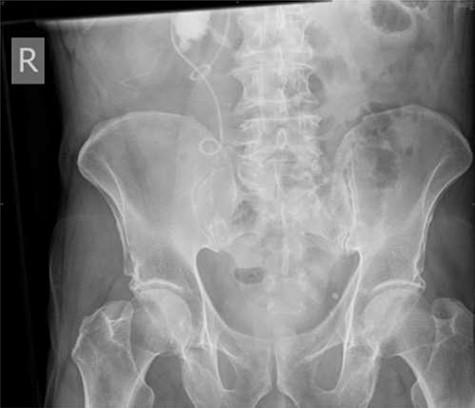

Seven months after the patient’s initial presentation, they underwent a laparoscopic right hemicolectomy; intra-operatively, a 6Ch/24 cm stent was inserted into the right ureter by the colorectal surgeon who had good experience of ureteric stent placement. The position of the stent was confirmed with cystoscopy and retrograde pyeloureterogram (Fig. 2).

Retrograde pyeloureterogram confirming position of right ureteric stent.